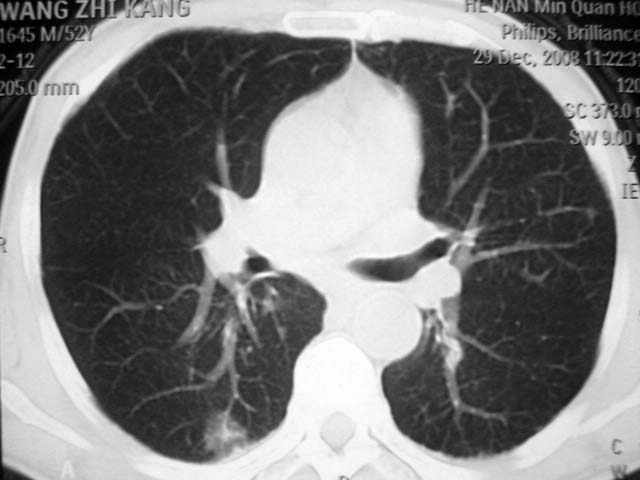

男,52岁,发热2月,糖尿病史。

抗结核治疗irpz方案,血糖未治疗,空腹15.9左右。症状无好转,左胸痛。

2、双肺见多发片状及结节状高密度影,大多数病灶中心均见“空泡征”。

3、纵隔内淋巴结肿大。

结果:两肺继发性肺结核并曲霉菌感染。